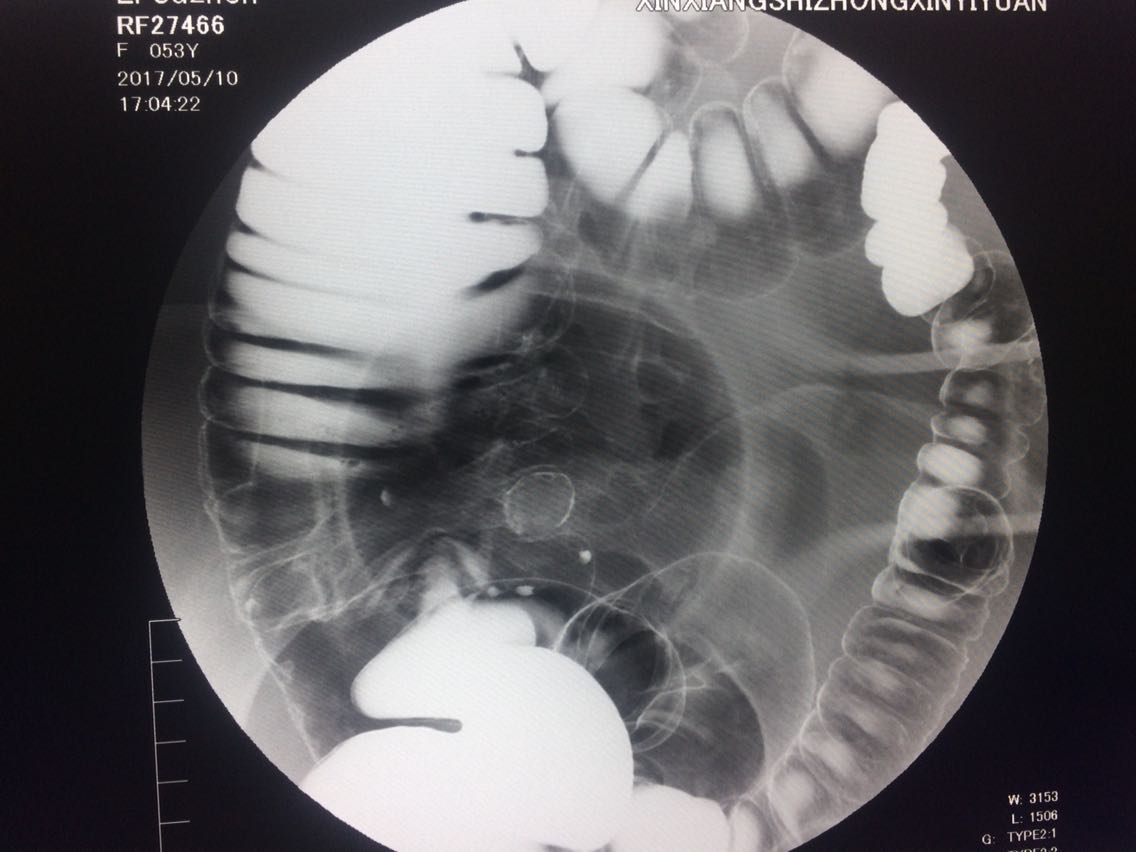

间断右下腹疼痛6年余。 6年来,无诱因出现右下腹痛,间断发生,呈胀痛,可忍受,压痛,无反跳痛。 既往:3年前,做肠镜未见明显异常。

查体,右下腹压痛。 入院做钡灌肠造影。

考虑升结肠占位。 完善术前各项检查。手术治疗。